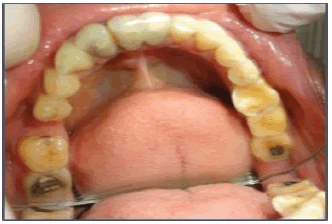

A Male patient aged 48 years old reported to the department of prosthodontics and Crown and Bridge. AB Shetty memorial institute of dental sciences, NITTE (Deemed to be University) Deralakatte, Mangalore. 575018 with the chief complaints of overall sensitivity of upper and lower teeth due to which he was unable to eat or drink cold and hot food. The patient also complained of compromised facial appearance due to the shortening of upper and lower teeth. A detailed case history was obtained which revealed that the patient had a habit of clenching and tooth grinding habit. Figure 1 illustrates the lost vertical dimension. Figure 2 illustrates the generalized attrition of the mandibular teeth. Figure 3 illustrates the generalized attrition of the maxillary arch. The Intraoral examination revealed a generalized loss of enamel and dentinal structure with a loss of 3 mm-4 mm of vertical dimension which was evident without any history of temporomandibular joint disorder. The treatment planning was formulated involving oral prophylaxis, followed by restoration of carious teeth, following which full-mouth rehabilitation was carried out by restoring the whole of maxillary and mandibular dentition with porcelain-fused-to-metal crowns at an increased vertical dimension of occlusion with 4 mm raised occlusal scheme with canine-guided occlusion to improve the aesthetic and functional value of the patient. The objectives of treatment planning were to attain functional harmony, re-establish aesthetics, and function, incorporate a canine-guided occlusal scheme, and enhance the health of the stomatognathic system. A heat cure acrylic splint was fabricated and was given to the patient to wear for 6 weeks. The adaptation of the patient to the increased vertical dimension at occlusion was evaluated at the interval of every 2 months. The patient gave no history of temporomandibular discomfort and Muscle tenderness. Occlusal interferences were corrected intraorally until the centric relation was harmonized with the centric occlusion. A Lucia jig was made with an established vertical dimension of occlusion at 4 mm Figure 4. The interocclusal bite record and protrusive bite record were made with bite registration wax (ALUWAX) Figure 5. The diagnostic impressions of maxillary and mandibular arches were made with a hydrocolloid impression material. The casts retrieved from the impressions were checked for finer details of teeth following which the cast was mounted on a semi-adjustable (Artex) articulator with a record of facebow transfer at an established vertical dimension of occlusion Figure 6. The mandibular occlusal plane was analyzed using Broadrick’s occlusal plane analyzer Figure 7. The marking on the Broadrick occlusal plane analyzer was opened at 4 inches, a mark was obtained on the flag with two points, one point at the distal slope of the canine and the other point at the distobuccal cusp of the second molar crossing the first point. Following which, another end of the divider was kept on this intersection of the marks, and the occlusal plane was marked mandibular case. on a semi-adjustable articulator (Artex) was programmed to Condition 1 of Hobo’s twin-stage procedure, wherein after removal of the maxillary anterior segment, posterior segment diagnostic wax-up was done in bilaterally balanced occlusion. The settings in condition 2 were changed by replacing the maxillary anterior segment with the wax-up for proper anterior guidance following which the disocclusion was achieved in eccentric movements in canine-guided occlusion. Table 1 showed the values of the hobo twin stage technique. Provisional crowns were fabricated with auto polymerizing resin using a vacuum-formed matrix produced from the diagnostic wax-up. The corrected occlusion was transferred to a customtailored anterior guide table fabricated with acrylic resin (Pattern Resin; GC Corp., Tokyo, Japan). Tooth preparation of all maxillary teeth was carried out in Figure 8, bite registration of prepared teeth was obtained in Figure 9, and Tooth preparation of all mandibular teeth was carried out in Figure 10. and the definitive twoâ??stage doubleâ??mix impression was made with polyvinyl siloxane elastomeric impression material (Aquasil and Dentsply) Figure11 and Figure 12. The interocclusal record was made with interocclusal recording material at an established vertical dimension, and Facebook was used for the recording of orientation jaw relation. Provisional restoration of the prepared tooth was done with temporary crowns (Protemp) that were cemented with soft zinc polycarboxylate temporary luting cement Figure 13 and Figure 14. After the cast was retrieved from the trays the die-cutting was made, and the casts were further mounted on an articulator (Hanau H2). The wax patterns were made with crown wax, the patterns were further invested, and the casting procedure was followed Figure 15. The try-in of metal copings was done in Figure 16. Following the ceramic build-up on all the metal copings the bisque try-in was done. The teeth were restored with The Porcelain-fused-to-metal restorations in Conditions 1 and 2 of Hobo’s technique. The canine-guided occlusion was checked in the mouth, and after verification, the crowns were cemented with temporary polycarboxylate cement. After the follow-up of 2 weeks, the patient’s response was recorded whether if comfortable with restored teeth. The crowns were cemented with resinâ??modified glass ionomer cement left side Figures 17 (FujiCEM; GC America, Alsip, USA) The crowns were cemented with resin-modified glass ionomer cement right side Figures 18, The frontal view of cemented crown Figures 19. Oral hygiene instructions were given and patients were advised to visit the department for regular follow-ups and check-ups.